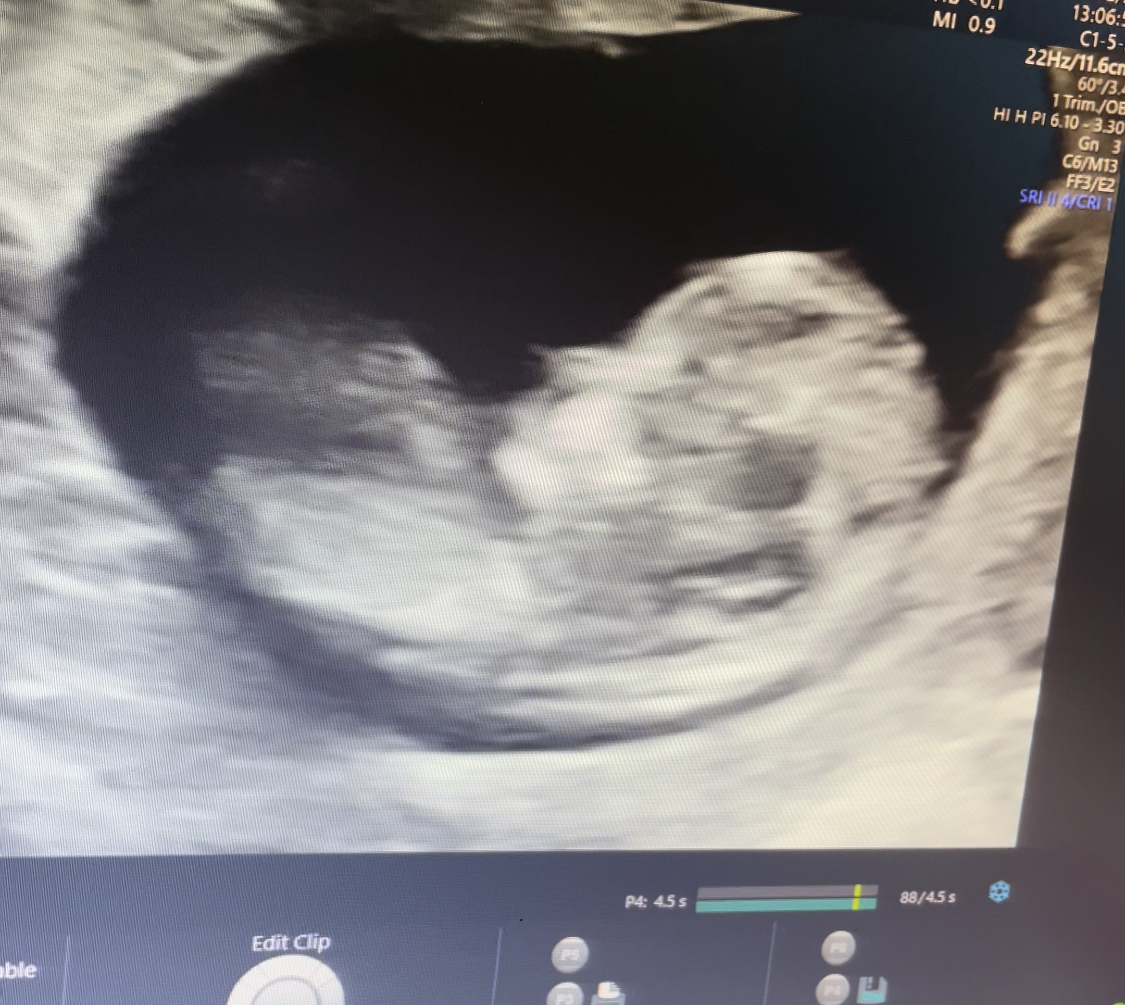

من دیروز رفتم سونوگرافی اول (nt غلبارگری ) جنسیت بچه رو نتونست حدس بزنه

میخواستم ببینم شما میتونید از رو عکس سونو حدس بزنید 🙂 صرفا جهت سرگرمی بنده 🌺🌹🙏🏻 الان عکس و میزارم

چند هفته شه؟😍